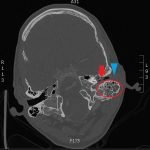

Significant findings:

The patient underwent computed tomography (CT) of the head which revealed opacification of the left middle ear (red arrow) and mastoid air cells (red circles). Additionally, there was thickening of the soft tissues of the external auditory canal (blue arrowhead), likely reflecting concurrent otitis externa.  Based on the imaging, he was admitted for findings consistent with acute otomastoiditis.